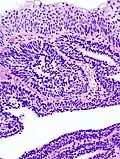

Inverted Schneiderian Papilloma of the Nasal Cavity. -

Inverted Schneiderian Papilloma of the Nasal Cavity with Abundant intraepithelial microabscesses.